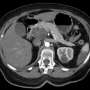

The pancreas, a vital gland located behind the lower part of the stomach, plays a critical role in producing hormones that regulate blood sugar and enzymes essential for digestion. When this organ develops cancer, early detection becomes paramount.

Latest data shows that pancreatic cancer often goes unnoticed in its early stages due to subtle symptoms that many may dismiss. These include unexplained weight loss, jaundice, abdominal pain, and sudden onset of diabetes. As these symptoms can be easily overlooked, health experts urge individuals to be vigilant and proactive in seeking medical advice if they experience any of these warning signs.